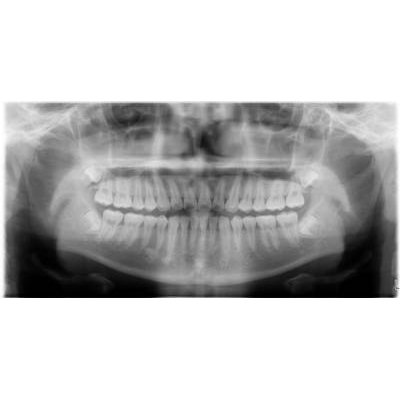

兒童牙科

乳齒:嬰兒出生後第六個月左右第一次長出來的牙會長滿20顆。

在周歲前開始定期牙科檢查

預防重於治療。通常在幼兒時期最常見的疾病-齲齒」。愈早作牙齒檢查,便有愈多的機會提早預防牙齒的發生。看牙不一定會痛!在沒有任何的病痛查,對幼兒來說,是一次的愉快經驗。

人工植牙